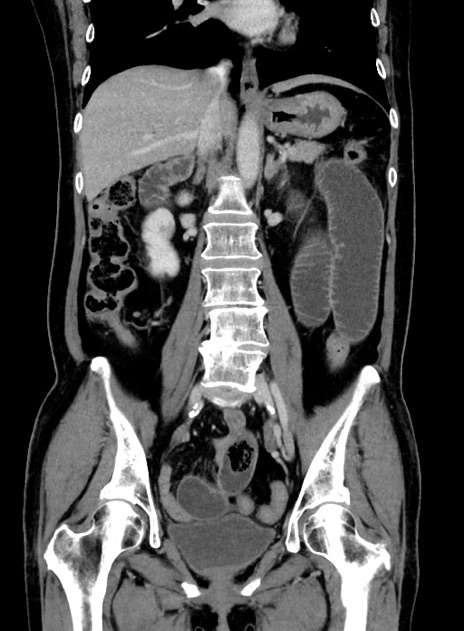

症例9(冠状断像)

【症例】 60歳代女性

【主訴】むかつき、みぞおちの痛み

【現病歴】3日前よりむかつきがあり、食事がとれない。

【既往歴】糖尿病

【身体所見】発熱なし、心窩部圧痛軽度あるも、腹膜刺激症状なし。

【データ】WBC 7400、CRP 1.92